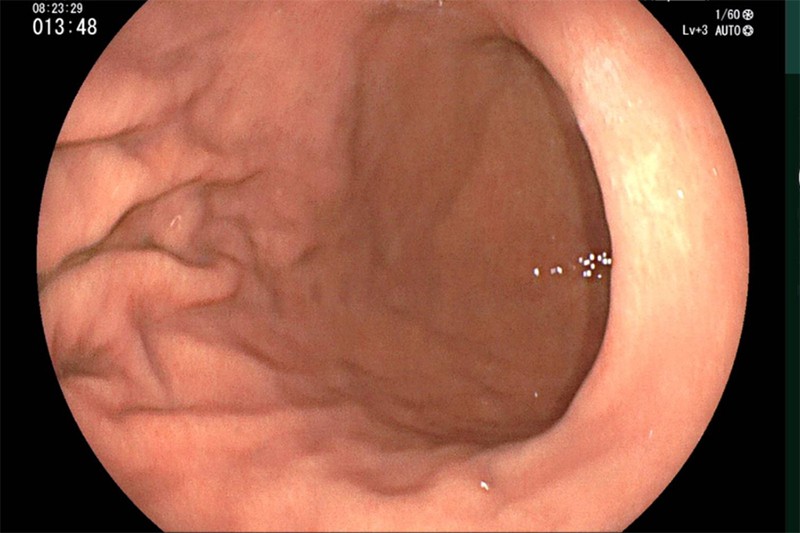

Hệ thống nội soi hiện đại tại Bernard giúp bác sĩ quan sát rõ từng tổn thương niêm mạc ruột

Một ca nội soi tiêu hóa tại Bernard cho thấy niêm mạc nhợt, mỏng, lộ rõ mạch máu